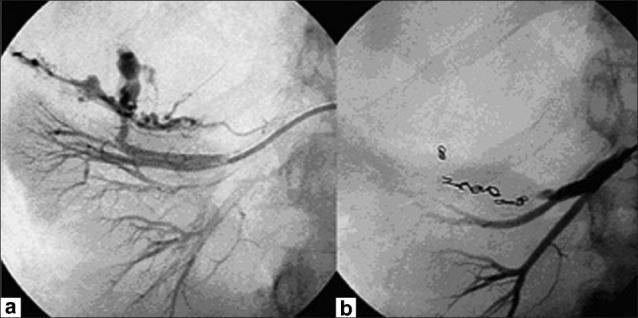

We report a case of Wunderlich's syndrome in an obese woman associated with massive retroperitoneal hemorrhage. Stable hemodynamic patient condition was obtained by selective arterial embolization. Since the first embolization of a renal angiomyolipoma in 1976 by Moorhead et al., highly selective renal arterial embolization of angiomyolipoma with rupture has become a procedure that offers greater efficacy, particularly in life-threatening cases.

我们报告一例肥胖女性的肾血管平滑肌脂肪瘤破裂综合征伴大量腹膜后出血。通过选择性动脉栓塞使患者血流动力学状况稳定。自1976年Moorhead等人首次对肾血管平滑肌脂肪瘤进行栓塞以来,对破裂的肾血管平滑肌脂肪瘤进行高选择性肾动脉栓塞已成为一种疗效更佳的治疗方法,尤其是在危及生命的病例中。